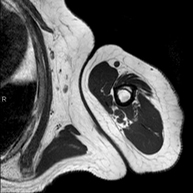

- RM d'Espatlla

Exploració per a l'estudi de lesions en els tendons, els músculs i les articulacions. La seva principal utilitat resideix en diagnosticar les lesions dels tendons del braçal rotatori. Té una durada aproximada de 20 minuts. No utilitza radiació ionitzant. - RM de Braç